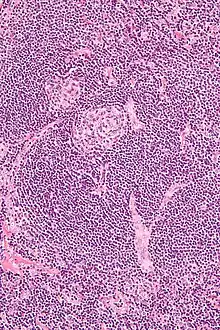

| Micrograph of Castleman disease showing hyaline vascular features including atrophic germinal center, expanded mantle zone, and a radially penetrating sclerotic blood vessel ("lollipop" sign). H&E stain. | |

- Hyaline vascular: regressed germinal centers, follicular dendritic cell prominence or dysplasia, hypervascularity in interfollicular regions, sclerotic vessels, prominent mantle zones with an "onion-skin" appearance.[14]